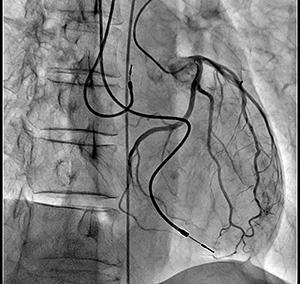

左冠動脈造影画像

※ノイズが少なく明瞭なコントラストで血管が造影される。

SCORE PRO Advanceは,リアルタイムの高画質化処理として従来のSCORE PROで培われたマルチ周波数処理・エッジエンハンス処理に加えて新たにモーショントラッキング(動き追跡)型ノイズ抑制処理を可能にした。これにより残像とノイズが低減し,フレームレートを従来の半分(15fpsから7.5fps)にしても血管内治療に求められる画質を十分確保し,結果的に被ばく線量を1/2に低減することが可能になる。

左 SCORE PRO Advance 透視画像 7.5fps

撮影よりも低線量の透視において,更に半分のフレームレートでも十分な視認性を確保している。